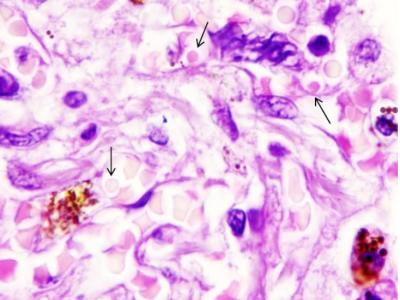

Cette attaque massive des globules rouges entraînerait des dommages aux neurones cérébraux, aux vaisseaux sanguins et aux organes internes, dont la fibrose pulmonaire serait l’une des manifestations les plus évidentes mais pas la seule (Visuel FEFU press office)

C’est une attaque bien plus systémique que pulmonaire, que décrit aujourd’hui cette équipe composée de scientifiques russes et japonais : le coronavirus SARS-CoV-2 s’attaquerait en effet à a moelle rouge et bloquerait la formation de nouveaux érythrocytes (ou globules rouges). Cette attaque massive des globules rouges entraînerait des dommages aux neurones cérébraux, aux vaisseaux sanguins et aux organes internes, dont la fibrose pulmonaire serait l’une des manifestations les plus évidentes mais pas la seule.

C’est pour cette raison que les cellules du système immunitaire et des mégacaryocytes, de très grandes cellules de la moelle osseuse, ont été trouvées dans les tissus de divers organes. Normalement, les mégacaryocytes produisent des plaquettes sanguines, qui sont responsables de la coagulation du sang, mais avec le COVID-19, ils coagulent le sang dans les vaisseaux sans aucune nécessité.

Ainsi, la fibrose pulmonaire n’est qu’une manifestation plus évidente du COVID-19, causée elle-aussi par un excès de mégacaryocytes dans la circulation sanguine et des processus similaires peuvent se produire dans les tissus de tous les organes parenchymateux (denses), à savoir les poumons, le foie, la rate, les reins, le pancréas et la thyroïde.

Ces scientifiques ont vérifié ces processus sur des échantillons de poumons de 79 patients décédés du COVID-19.